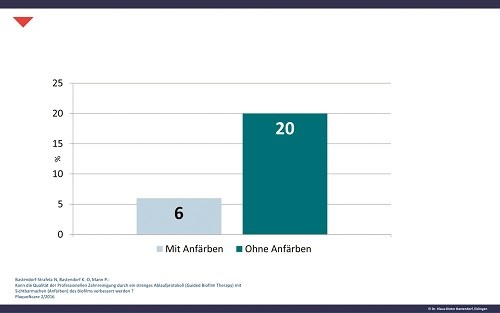

Только индикация зубного налета позволяет полностью (95–100 %) устранить наддесневую биопленку.7 Этот факт также подтверждает исследование, проведенное Stiftung Warentest (независимая экспертная организация, осуществляющая потребительские испытания) относительно качества профессиональной чистки зубов (PTC – Professional tooth cleaning) в 10 стоматологических клиниках. Без применения индикации зубного налета удалось устранить только приблизительно 50 % биопленки. В частности, обнаружено недостаточное удаление в критических местах (в пришеечной области и в межзубных пространствах). Биопленка является причиной развития наиболее распространенных стоматологических заболеваний. Индикацию биопленки необходимо проводить для:

Примечание: Без применения индикации зубного налета даже очень опытный специалист может оставить в три раза больше поддесневой биопленки (рис. 3).8 Этот факт тоже был доказан во время вышеупомянутого исследования, проведенного организацией Stiftung Warentest. К тому же, обеспечение минимально инвазивного воздействия возможно исключительно после применения индикации, т.e. происходит только удаление наддесневой биопленки без избыточного воздействия на эмаль и дентин.

Рис. 3. Наддесневое удаление биопленки с (6) и без (20) ее предварительной индикации (измерения проведены с помощью Plaque Control Record по O‘Leary и соавт. 1972)